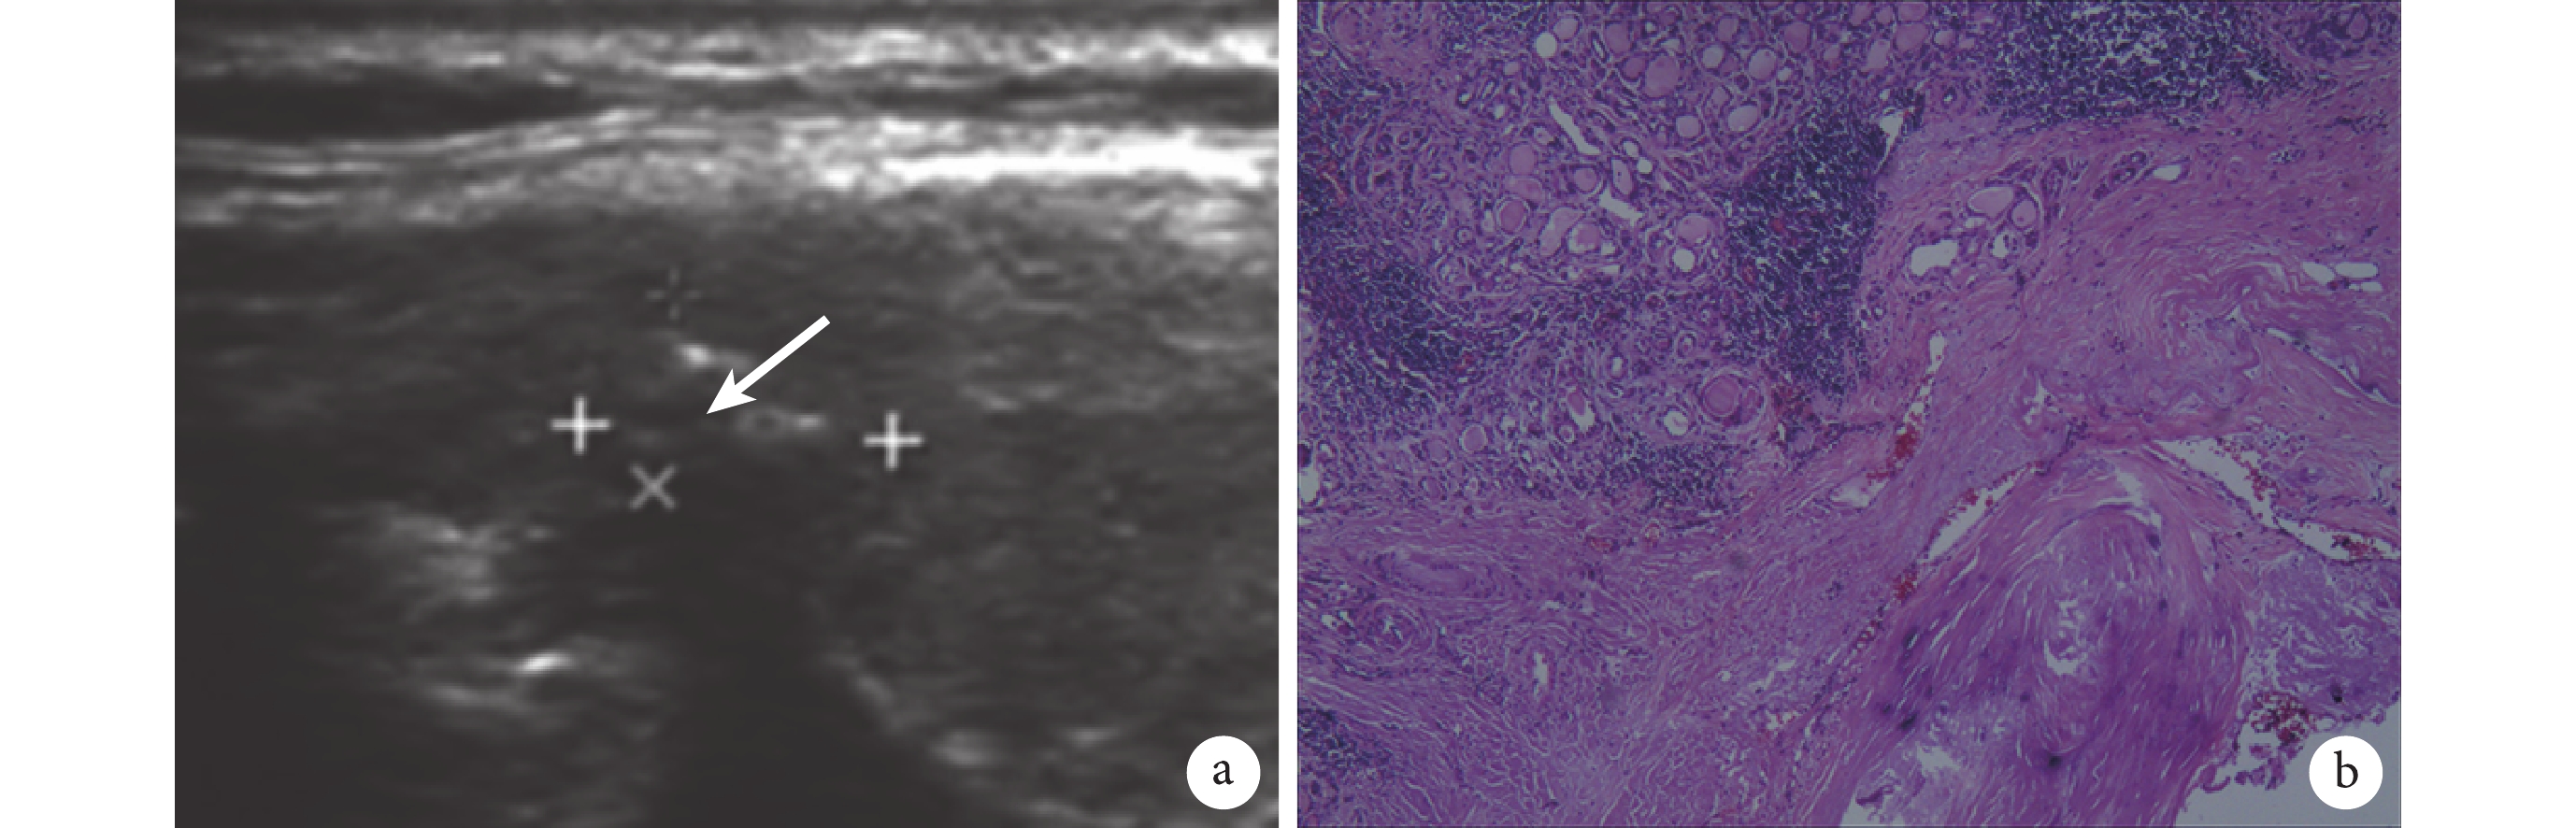

a:超聲圖像見甲狀腺內一低回聲區(白箭),約 1.7 cm×0.9 cm 大,邊界欠清,形態欠規則,內部回聲欠均,內見點狀強回聲,結節內部未見明顯血流信號;b:顯微鏡下見結節性甲狀腺腫局部鈣化、纖維化(HE ×100)